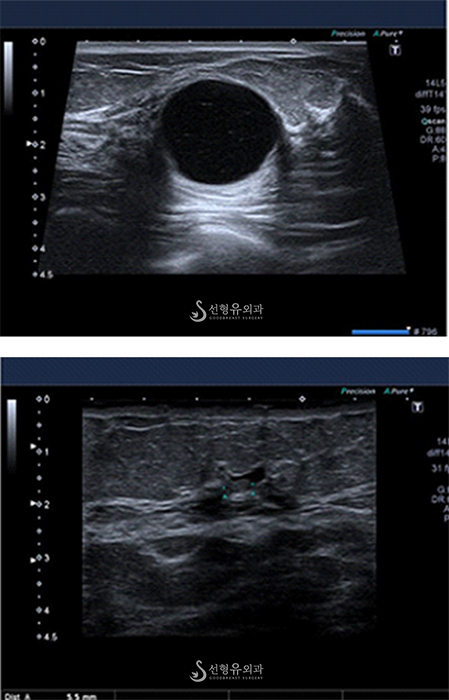

유방초음파 검사는 유방암 뿐만 아니라

단순 물 혹, 지방종, 섬유종 등의 크기가 작은 양성 종양까지 발견할 수 있습니다.

젊은 여성과 임산부에게도 안전하게 할 수 있기 때문에 유방에 이상 증상이 있을 때 뿐만 아니라 단순검진 목적으로도 많이 시행합니다.